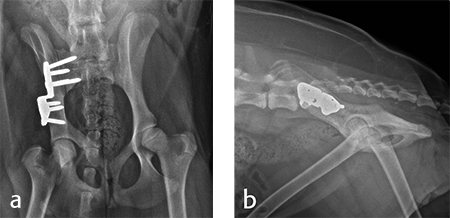

For each surgical procedure, the patient was placed in dorsal recumbency to enable the pubic ostectomy. The patient was repositioned in lateral recumbency to perform the DPO. A left ilial osteotomy was performed caudal to the sacrum. A 25° DPO/TPO plate was attached to the caudal ilial segment using locking 3.5 mm screws in the three stacked combi holes. The caudal acetabular segment was rotated laterally until the cranial aspect of the plate was in contact with the lateral aspect of the cranial ilial segment. The osteotomy site was compressed and the plate was secured to the cranial ilial bone segment using a 3.5 mm cortical screw in the LCP combi hole in the cranial side of the plate. Three additional 3.5 mm locking screws were placed in the remaining stacked combi holes in the cranial segment of the plate (Fig 9).

Activity was restricted to leash walks for 6 weeks postoperatively. The radiographic examination 1 month after each surgery revealed partial healing of the ilial osteotomy and stable implants. Postoperative radiographs at 6 months after both surgical procedures revealed complete healing of the ilial osteotomies, stable implants, and excellent coxofemoral conformation, with no subluxation of the femerol head. Mild osteoarthritis was observed, however. At both the 4 and 6 month evaluation, the dog was using both hind limbs without any evidence of lameness and was showing no signs of instability or pain of either hip (Fig 10).